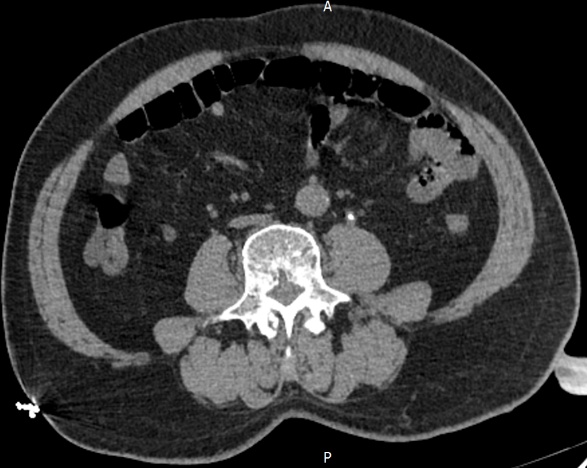

根据检查结果,最终以“泌尿系 CT 示左侧输尿管腹段结石(直径3mm)伴左肾盂积水及上段输尿管扩张”的诊断将侯先生收入住院,并告知家属侯先生的病情是十分危险的。

像上述文章里提到的侯先生就是尿源性脓毒血症最典型的症状,有高烧、寒战这些情况。泌尿系CT平扫示左侧输尿管腹段结石伴左肾盂及上段输尿管积水。考虑尿路梗阻感染引起的脓毒血症休克。